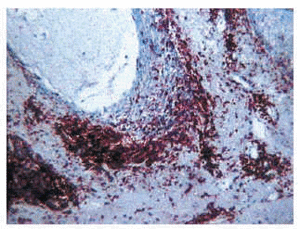

Los casos de mucinosis folicular urticarial fueron los más fácilmente identificables histológicamente. Los depósitos de mucina eran escasos; sin embargo, el infiltrado inflamatorio era muy abundante, siendo su localización superficial y profunda (incluso hasta tejido celular subcutáneo). El dato más característico era la gran abundancia de eosinófilos, significativamente superior a la de todas las otras formas clínicas definidas de mucinosis folicular (fig. 8). Los depósitos de mucina eran escasos.

Fig. 8.--Mucinosis folicular urticarial. Abundantes eosinófilos.